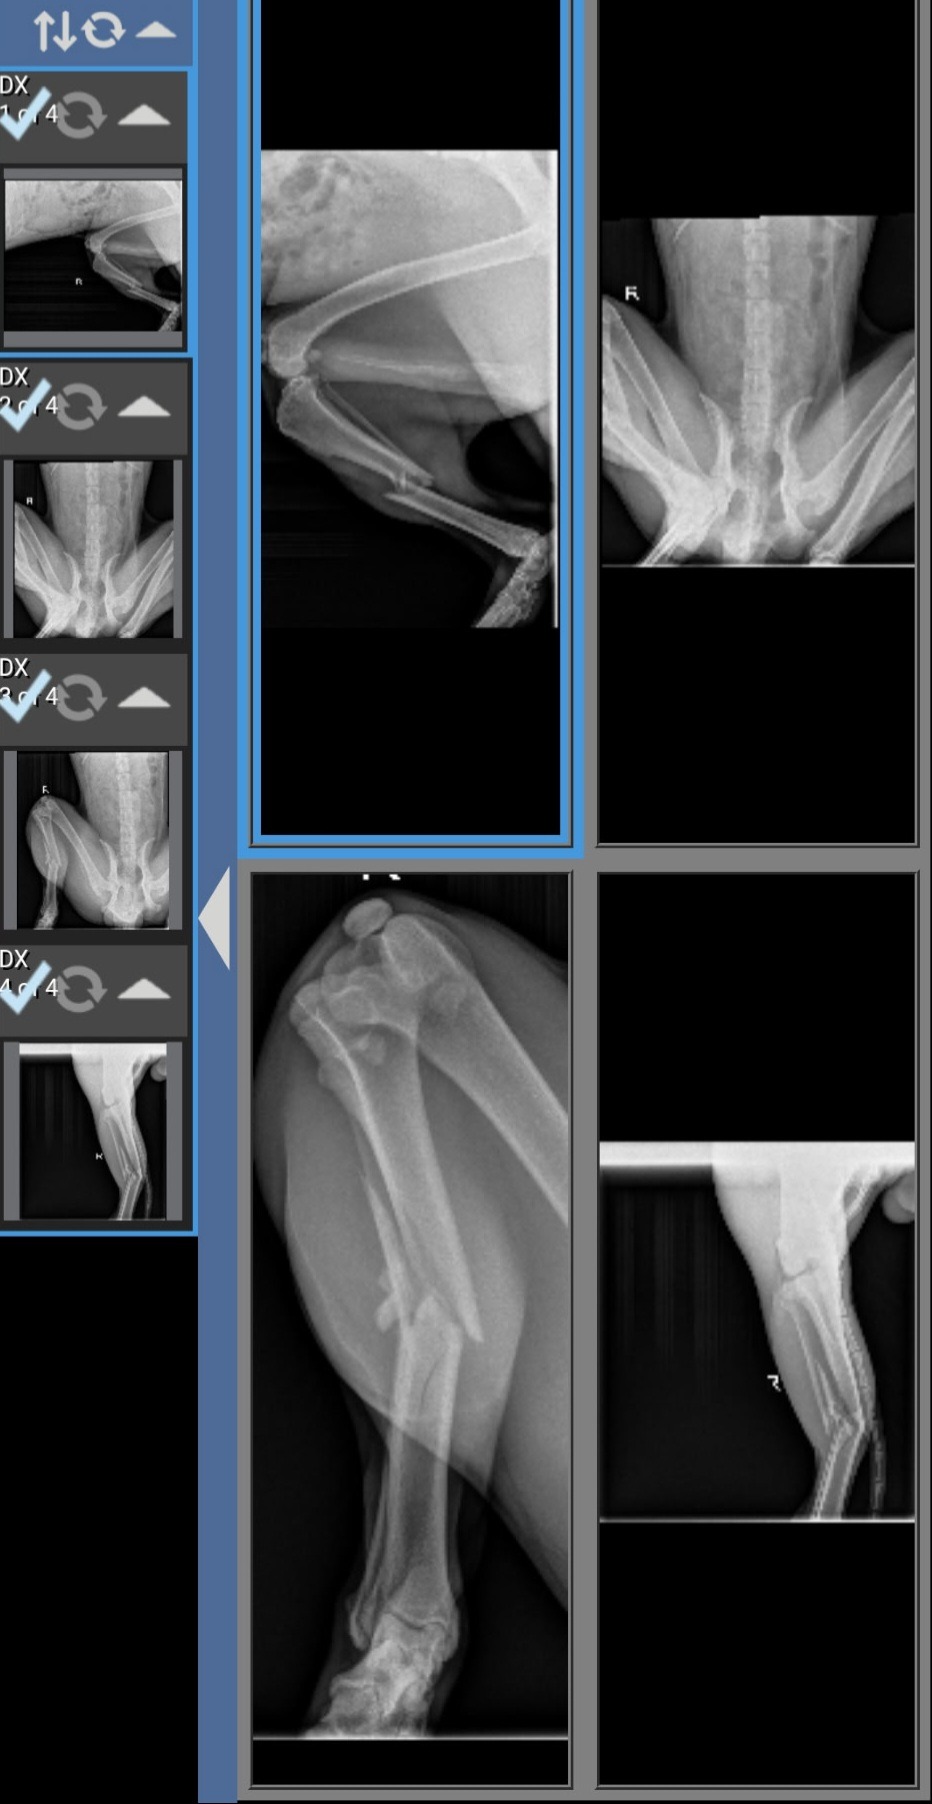

Description: Drax is a very high-energy, lovable, and loyal member of our family. He’s not just our pet, he’s my daughter’s best friend and her constant protector. Drax loves to play and bring joy to our home, but recently, he broke his leg while playing with my daughter. Since then, he hasn’t been able to run around or enjoy his favorite activities, and it’s been heartbreaking for all of us to see him in pain.

This accident has been especially hard on my daughter, who feels guilty even though we’ve reassured her that accidents happen. The sudden expense of surgery, medications, and ongoing vet appointments has been overwhelming for our family. We want nothing more than to see Drax healthy and happy again, chasing after toys and sharing special moments with us.